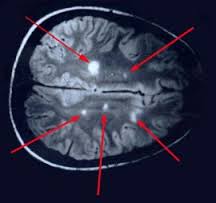

- МРТ. Этот метод весьма чувствителен. Но не очень точен.